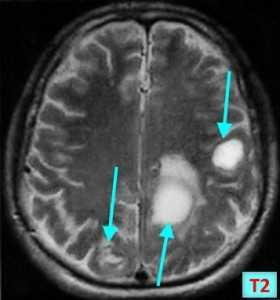

МРТ-признаки метастазов в мозг

МРТ — более чувствительный и специфичный метод в выявлении метастазов ЦНС по сравнению с компьютерной томографией. Вторичные опухоли имеют ряд общих черт при МР-исследовании.

Т1 ВИ (без контрастного усиления)

- Изоинтенсивный либо умеренно гипоинтенсивный сигнал по отношению к белому веществу мозга от активной части опухоли

- Гипоинтенсивный сигнал от центральной зоны (некроза и распада)

Т2 ВИ

- Гиперинтенсивный сигнал от центрального участка метастаза

- Повышение интенсивности сигнала от отечных тканей мозга, окружающих вторичную опухоль, вследствие чего метастазы становятся более четкими на изображениях

МРТ с контрастным усилением

- Выраженное увеличение интенсивности сигнала

- Усиление сигнала по периферии в виде «кольца» или «короны»

- Помогает дифференцировать кровоизлияиния в метастаз от геморрагического инсульта (выраженное усиление сигнала на Т1 ВИ)

Метастазы головного мозга на МРТ. Фото. Определяются множественные метастазы в мозг при раке легкого: слева в режиме Т1-ВИ в виде гипоинтенсивных образований, справа — в режиме Т2-ВИ виде множественных участков повышенного сигнала, окруженных зоной перифокального отека. У пациента подтверждена первичная опухоль легкого.